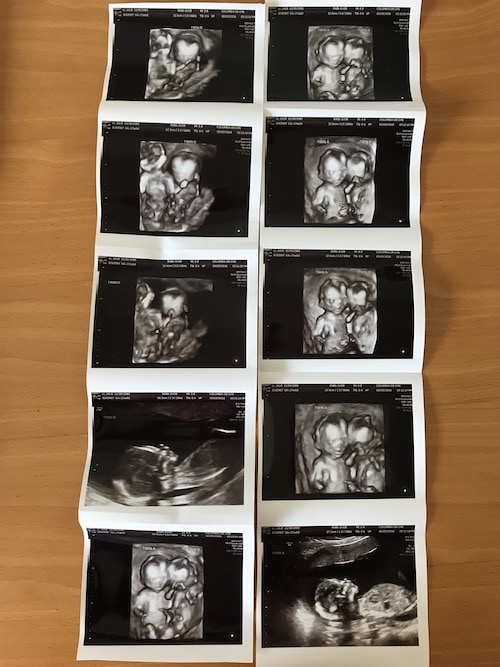

- Ultrasound Photos at 17 Weeks Pregnant With Twins

Ultrasound Photos at 17 Weeks Pregnant With Twins